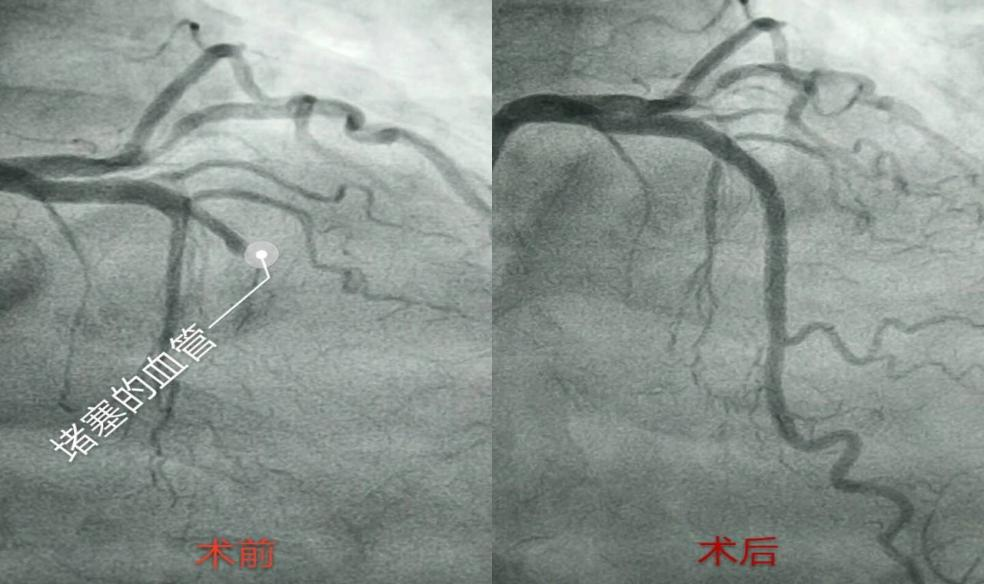

部分血栓碎片p-pci后,罪犯血管前降支血运重建,再灌注治疗成功ptca后